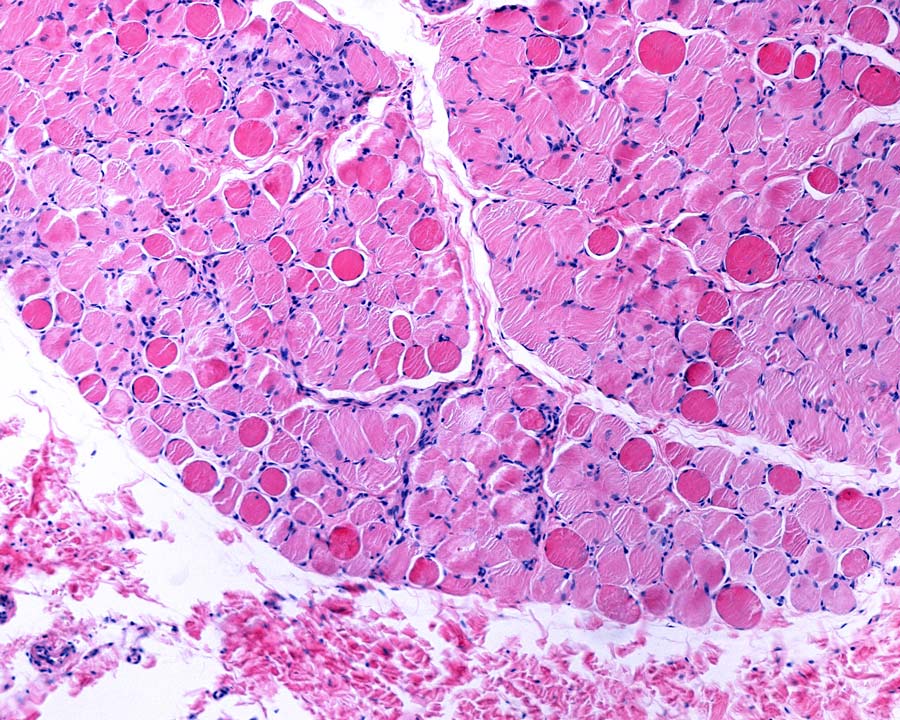

杜氏肌营养不良症(DMD)是一种基因突变引起的疾病,该基因会产生肌肉蛋白肌营养不良。肌萎缩蛋白在维持肌肉结构中起着至关重要的作用;对于患有DMD的人来说,肌萎缩蛋白的缺乏意味着肌肉的损伤会逐渐累积。

通常情况下,骨骼肌(即附着在骨骼上的肌肉)在受伤后具有显著的自愈能力。肌肉干细胞,特别是一种被称为卫星细胞的细胞,在愈合过程中起着至关重要的作用。因此,研究人员将卫星细胞作为治疗肌肉萎缩症的潜在途径。利用老鼠进行的研究已经产生了有希望的结果,移植的卫星细胞可以恢复肌营养不良和更好的肌肉功能。对DMD患者的研究已经开始;然而,在这成为一种广泛使用的治疗方法之前,还需要做更多的工作。

干细胞是一种有价值的工具,可以两种方式进行肌营养不良研究:通过作为疾病的模型,并在其作用中作为该病症的直接治疗。最近的工作表明,干细胞移植可能不仅可以恢复患有肌营养不良的人的营养不良蛋白功能,而且还可以恢复细胞环境,有效地限制疾病的进一步进展。与此同时,新的遗传技术如外汗跳跃,提供了不同的方法来解决像DMD等疾病背后的基因突变问题。